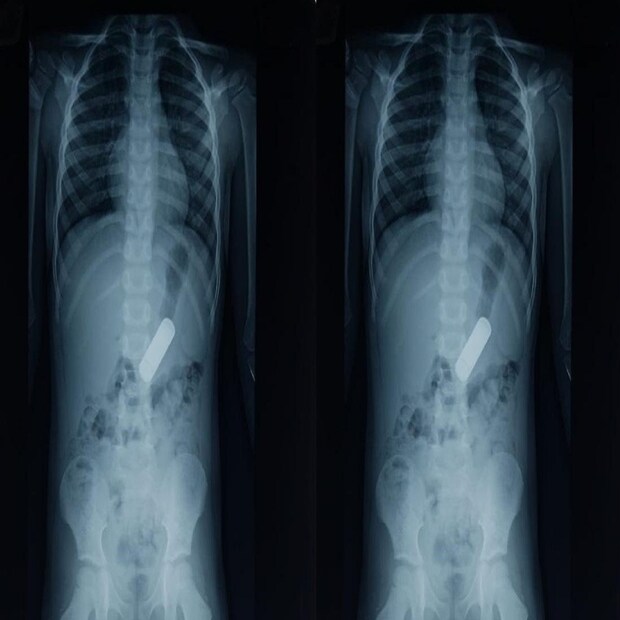

Doctors save 4years old Boy: ৪ বছরের বাচ্চার পেটে ৫ সেমি ব্যাটারি! ১৪ ঘণ্টার ম্যারাথন লড়াই শেষে চিকিৎসকেরা নতুন প্রাণ দিলেন শিশুটিকে

Viral News|Chennai News|National News: চিকিৎসকেরা প্রাণ বাঁচালেন একজন শিশুর ৷ ৫ সেমি ব্যাটারি গিলে ফেলাতেই বিপত্তি